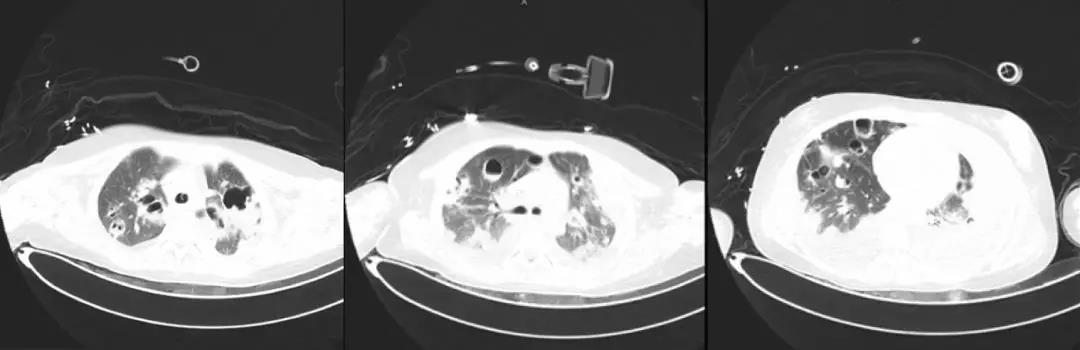

*影像学仍持续变化:

左侧胸腔病变为肺大泡?气胸?如何处理?药物是否需要调整?

*局部气胸引流

- 行左侧胸腔穿刺共两次,共抽出气体约2000ml;

- 患者呼吸困难缓解;

- 患者体温高峰逐渐下移;

- 复查血常规:白细胞9.79*10^9/L;降钙素原0.18ng/ml;血培养阴性